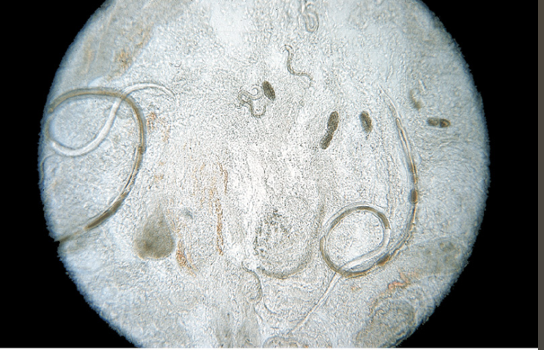

Toxocara canis

Toxocara cati

Toxascaris leonina

When Toxocara canis/cati are passed through the feces, the adult worms usually appear ___

tightly coiled